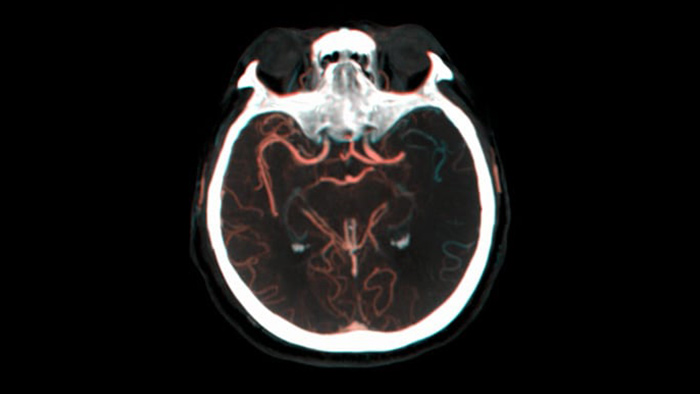

O SmartCT para Tecidos Moles gera uma visualização de tecidos moles semelhante à de uma tomografia computadorizada e facilita de três maneiras o diagnóstico de AVC: uma varredura sem contraste ajuda a detectar as primeiras alterações isquêmicas; uma varredura de fase inicial ajuda a identificar a oclusão proximal; e uma varredura aprimorada de fase avançada com contraste facilita a detecção dos fluxos sanguíneos colaterais.

O recurso SmartCT Vaso permite a visualização além do coágulo com o diagnóstico por imagem periprocessual dos aspectos do vaso distal no AVC isquêmico. O SmartCT Vaso é uma técnica de aquisição baseada na Tomografia Computadorizada de Feixe Cônico e em uma injeção de contraste intra-arterial que permite a visualização além do coágulo com o diagnóstico por imagem periprocessual dos aspectos do vaso distal no AVC isquêmico. Por meio do preenchimento retrógrado, as estruturas dos vasos antes e depois do coágulo tornam-se visíveis. O Roteiro 3D do SmartCT Vaso pode ser usado para visualizar os dispositivos de recuperação de coágulos.

O recurso Dual View, para visualização lado a lado dos volumes anteriores e posteriores da Tomografia Computadorizada de Feixe Cônico, aprimora a identificação do efeito penumbra e permite a visualização do preenchimento colateral.